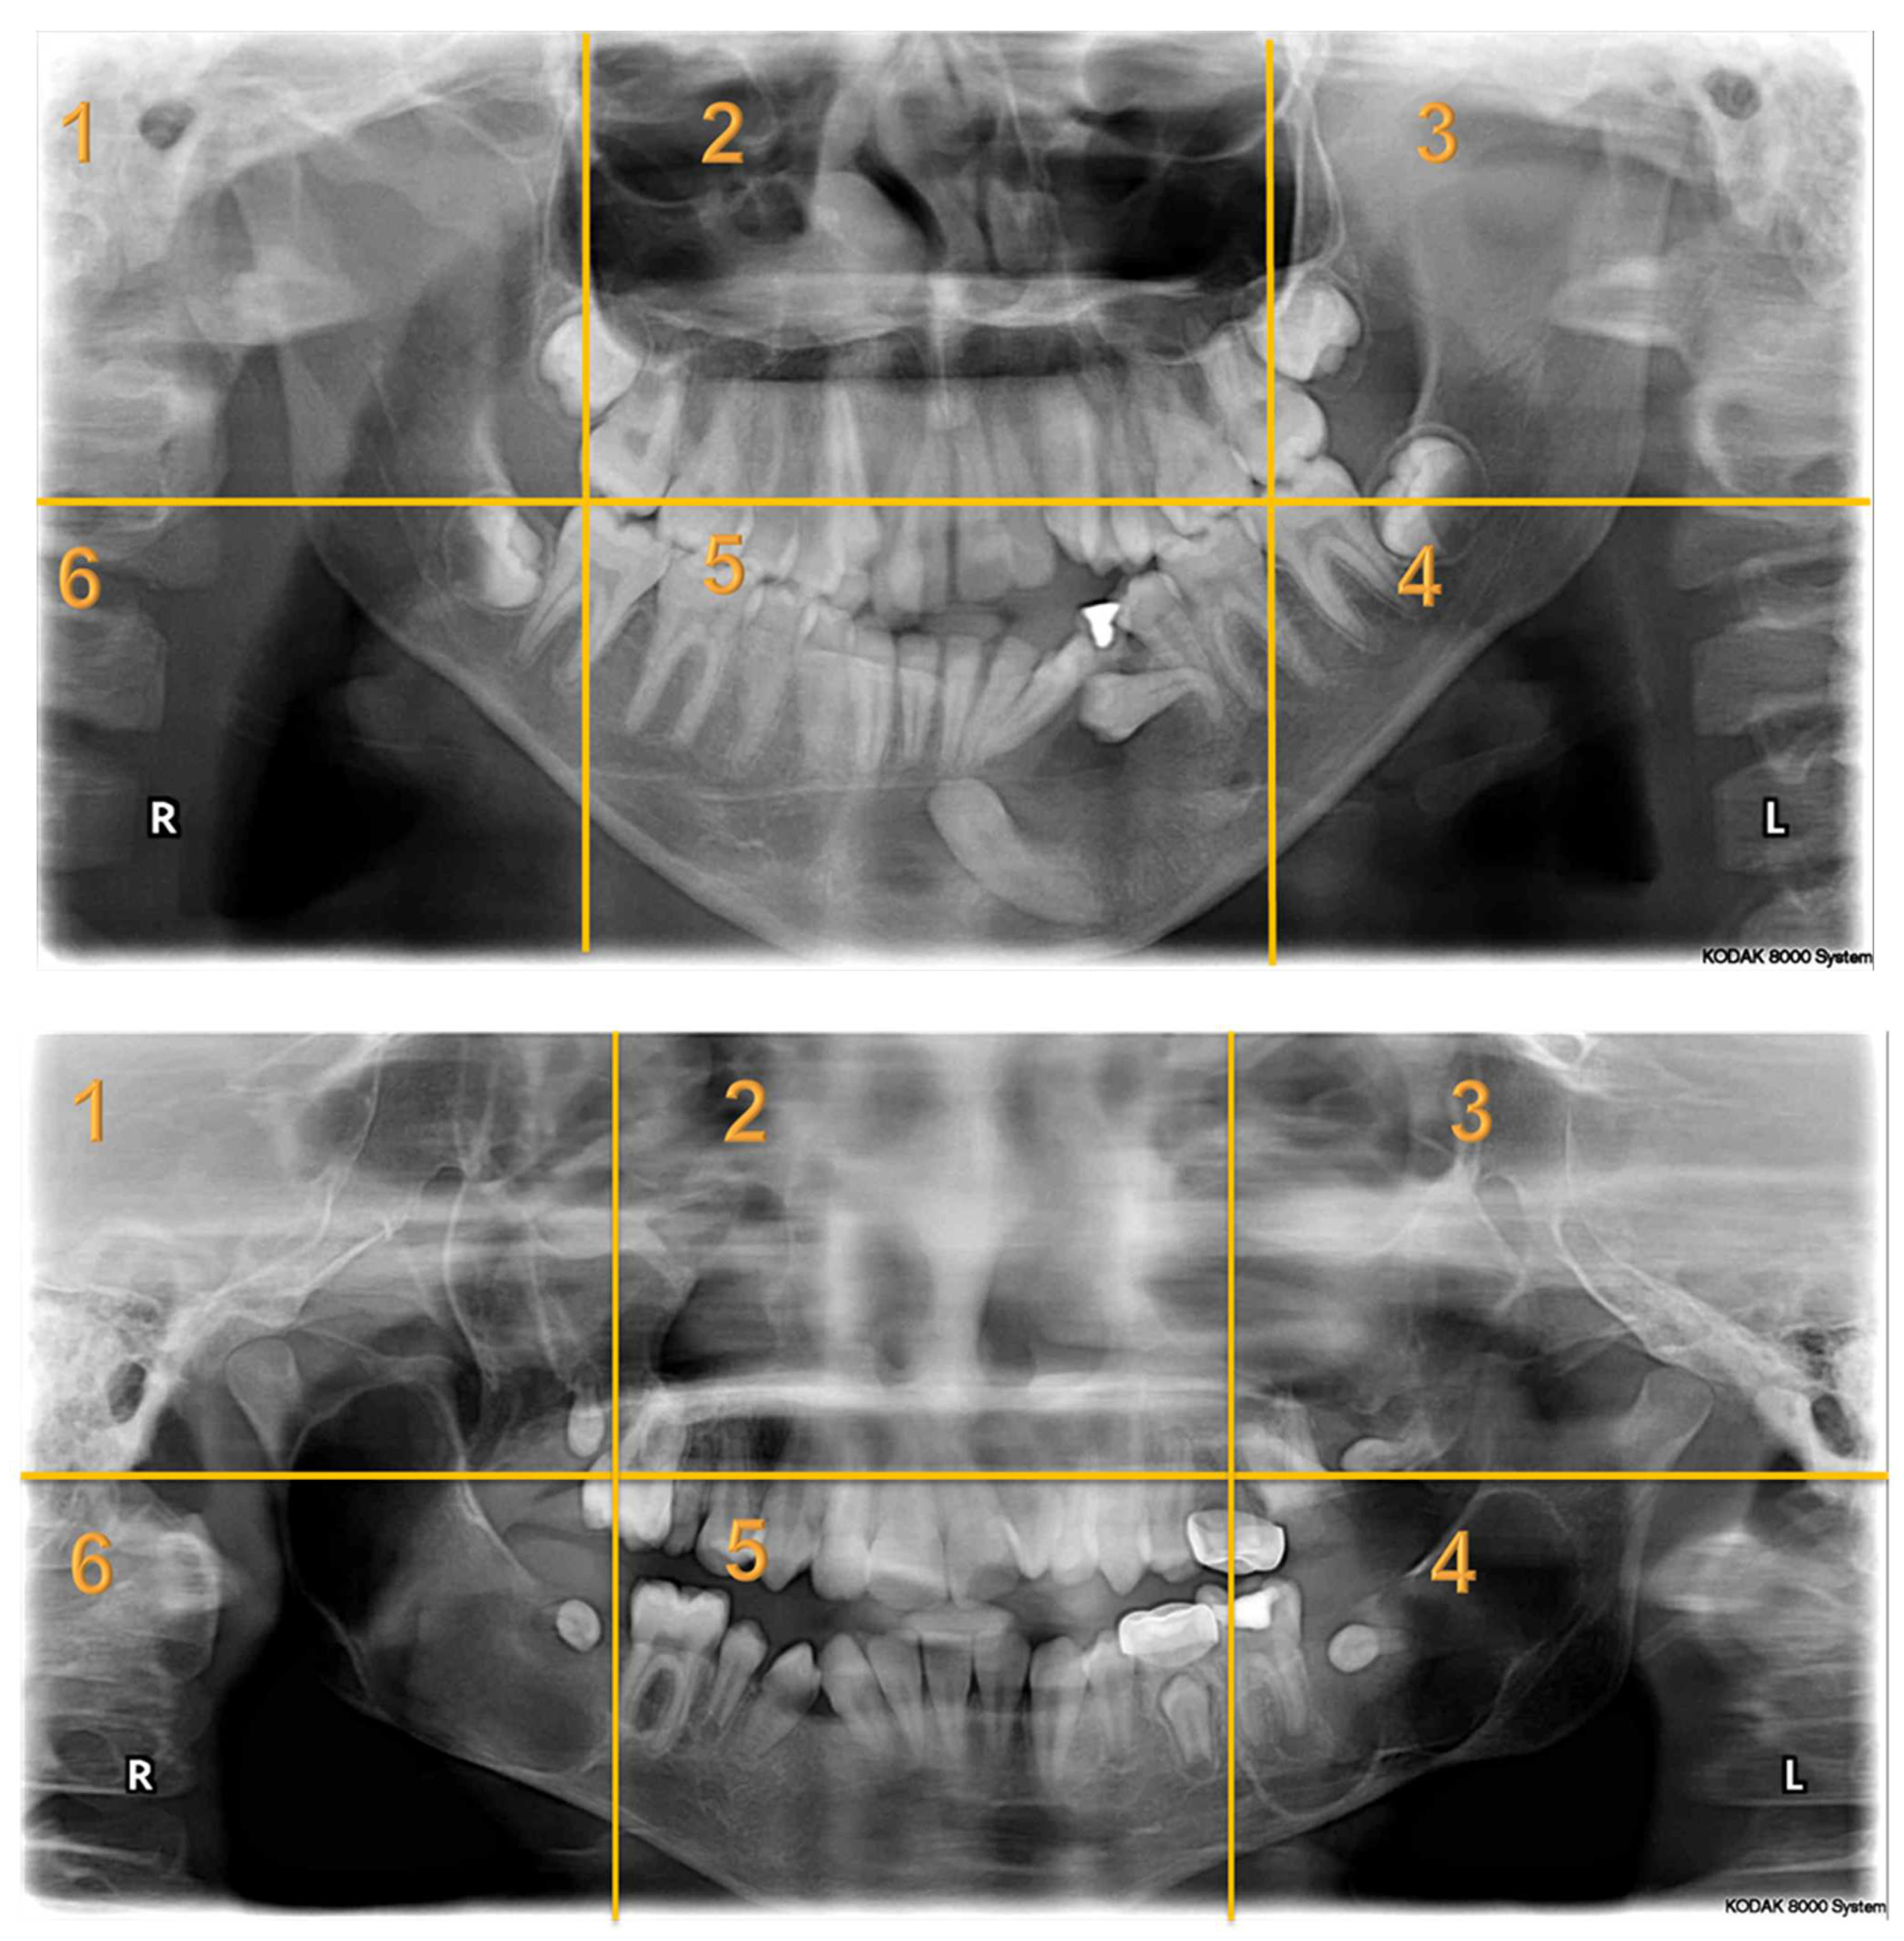

Appendix A. Radiographs Included in the Study

| Radiographs with Abnormalities | Number of Sextants Involved | Number of AOI a | Number of Participants | Total Recorded Observation b |

|---|---|---|---|---|

| Radiograph 1 | Multiple | 3 | 30 | 90 |

| Radiograph 2 | Multiple | 8 | 30 | 240 |

| Radiograph 3 | Single | 2 | 30 | 60 |

| Radiograph 4 | Single | 2 | 30 | 60 |

| Radiograph 5 | Single | 1 | 30 | 30 |

| Radiograph 6 | Single | 1 | 30 | 30 |

| Radiograph 7 | Single | 1 | 30 | 30 |

| Overall Observations | 540 |